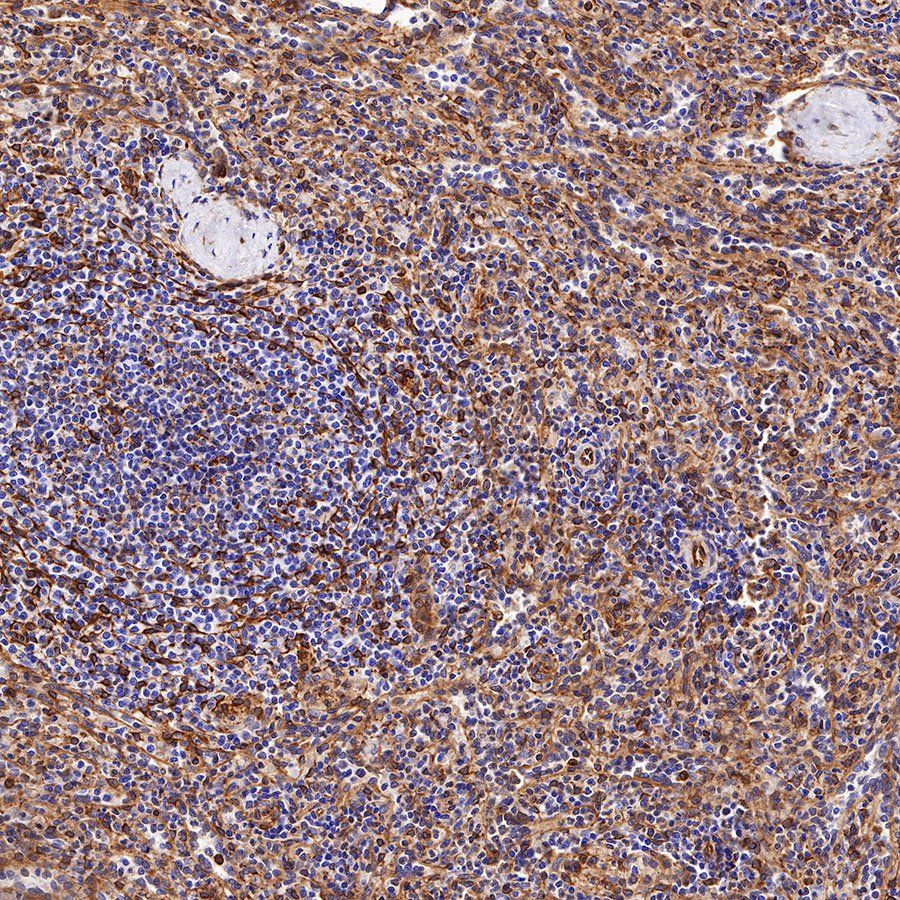

Picture

Picture

Immunohistochemistry